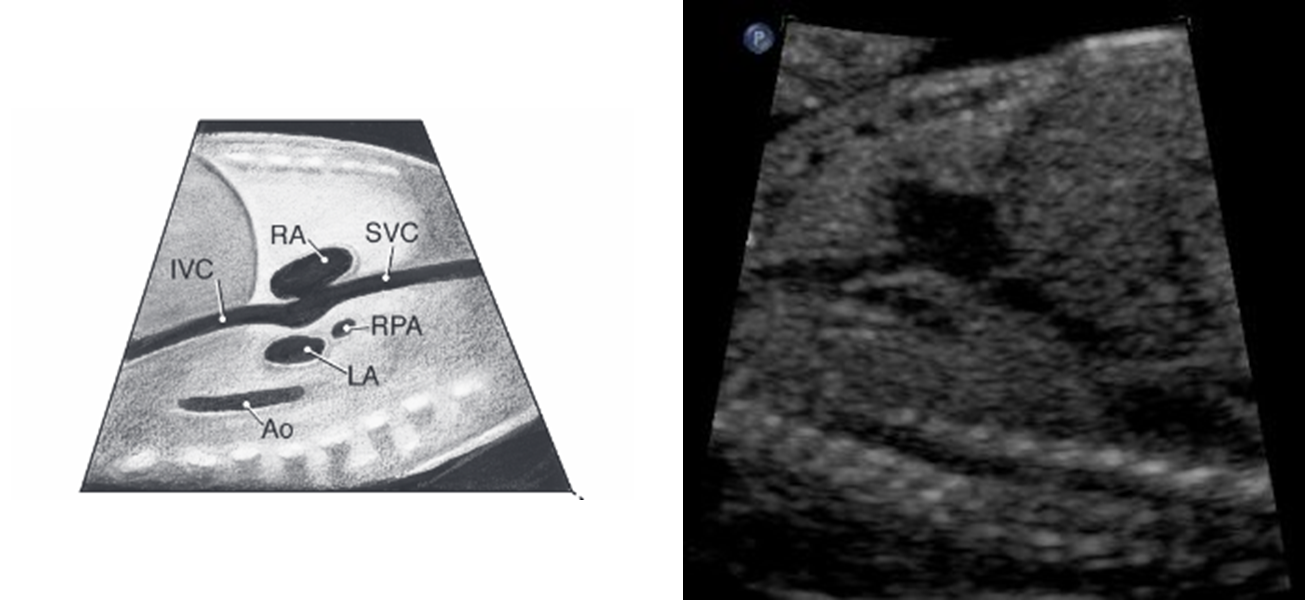

normally what is closest to anterior abdominal wall

right ventricle

what is closest to spine

left atrium

pulmonary veins drain into

there are 4 but we usually see 2

in-flow tracts

SVC/IVC